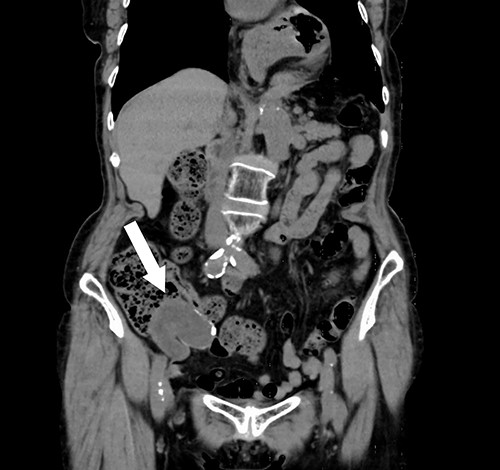

A 74-year-old female with hypertension, hyperlipidemia and hyperuricemia had a colonoscopy as a screening examination. The colonoscopy revealed an extrinsic compression with ulceration located at the cecum (Fig. 1). A multidetector computed tomography (CT) identified a low-attenuation distorted cystic lesion with focal calcification in the anatomic region of the right iliac fossa, measuring 6.1 × 5.0 × 3.7 cm (Fig. 2). Findings from the routine laboratory examinations were unremarkable, and all tumor markers were within normal range. The patient was scheduled for ileocecal resection with lymph node dissection due to the possibility of malignancy, such as appendiceal mucinous adenocarcinoma, because of the large and distorted tumor. Contrast-enhanced CT was conducted for further assessment of the findings, and we found that the cystic lesion was dramatically shrinking. It seemed improbable that rupture of the tumor had happened since no findings implied the spread of mucinous components, such as ascites or mucinous peritoneal nodules on CT. It was considered that the mucinous content was spontaneously drained from the root of the appendix to the cecum. However, the enhanced and distorted lesion with focal calcification, suggesting malignancy, had remained in concordance with the base of appendix (2.7 × 2.1 × 1.9 cm) (Fig. 3). Therefore, ileocecal resection was performed as planned, and laparoscopic procedure was selected due to the unlikelihood of the tumor rupturing. The base of appendix was distended and there were no obvious peritoneal anomalies upon visualization of the abdomen (Fig. 4). The specimen was handled with care and there was no spillage of cystic contents. The post-operative course was uneventful, and the patient was discharged on post-operative day 8.

Abdominal CT showing a cystic lesion with some calcification in the right iliac fossa (arrow).